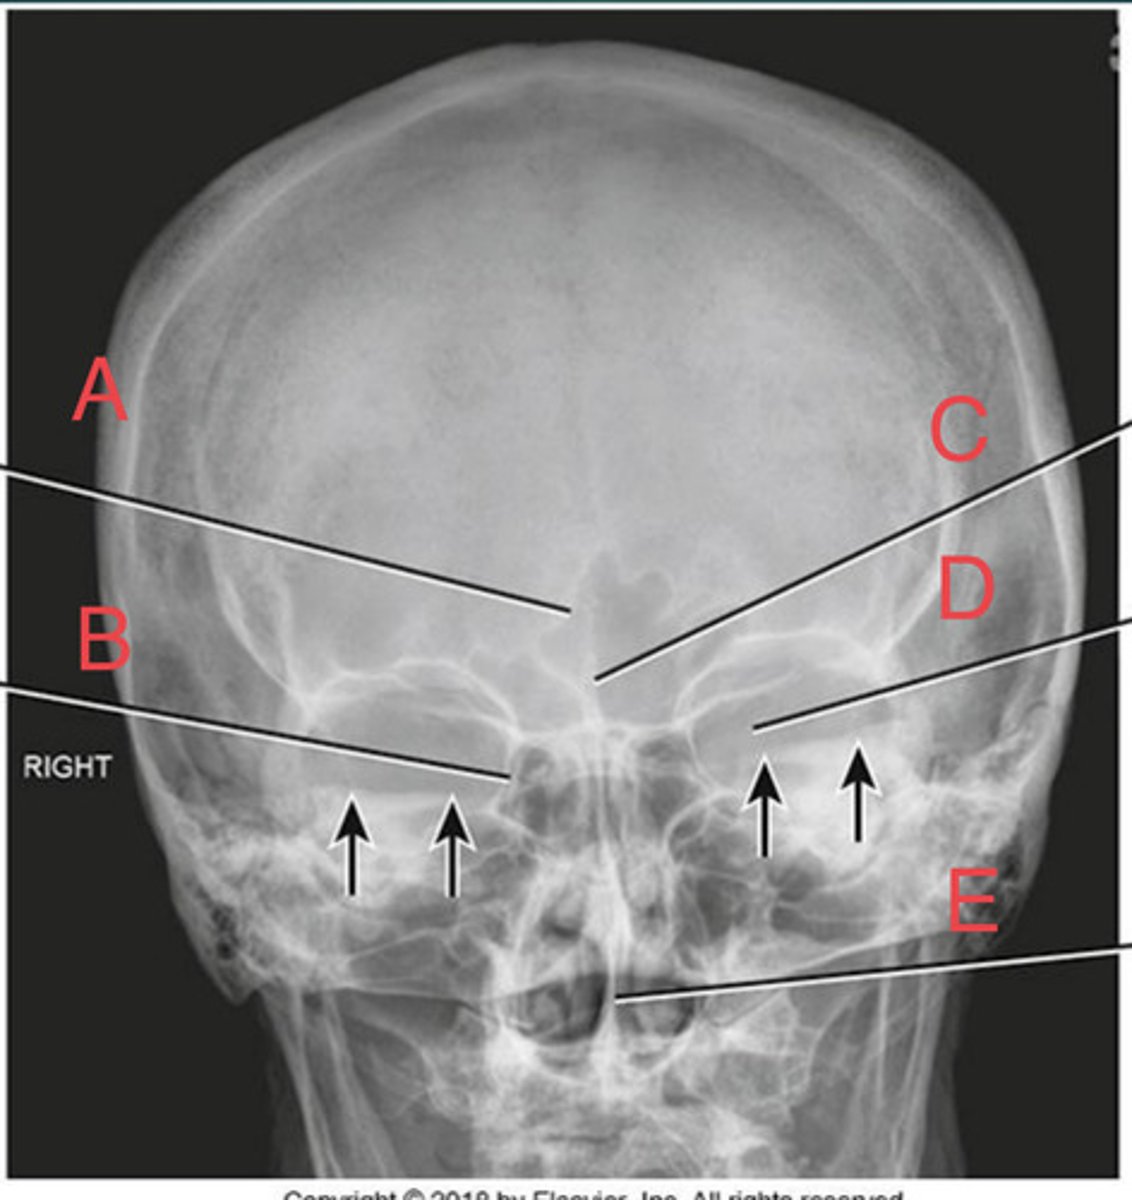

PA Caldwell Sinuses

What position?

frontal sinus of the frontal bone

A.

R. ethmoid sinus of the ethmoid bone

B.

crista galli of ethmoid bone

C.

L superior orbital fissure of the sphenoid

D.